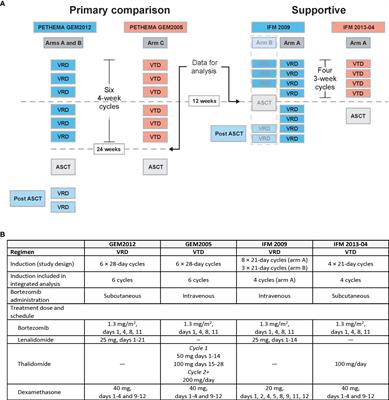

Integrated analysis of randomized controlled trials evaluating bortezomib + lenalidomide + dexamethasone or bortezomib + thalidomide + dexamethasone induction in transplant-eligible newly diagnosed multiple myeloma